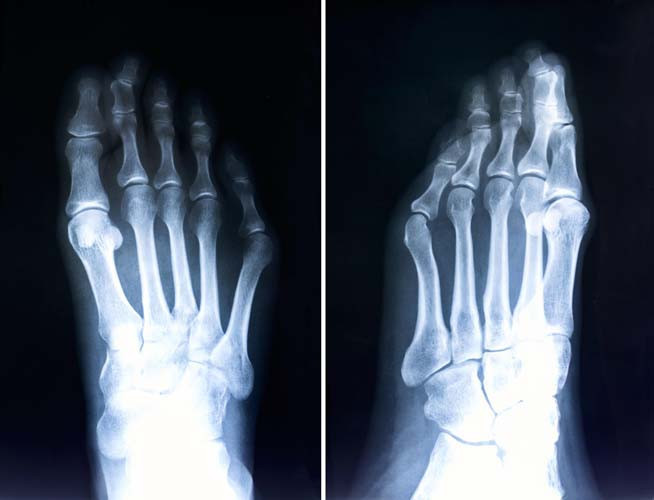

Hastanın ayağının görüntüsü tanı konulmasında yardımcı olmaktadır. Bununla birlikte üzerine yük verilmiş ayağın, yere basarken çekilen Röntgen filmi teşhise kesinlik kazandırır. Röntgen filmi ile başparmağın birinci tarak kemiğine ya da birinci tarak kemiğinin, ikinci tarak kemiğine olan açıları ölçülmektedir. Açı hesaplamalarının ardından uygun tedavi yöntemi seçilmektedir.